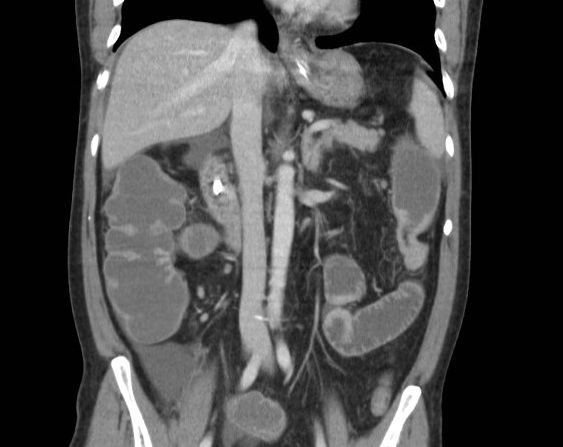

Aspect de distendue du plexus

splenique dans pancreatite aigue . Image

radiologique TDM avec contrast intraveineuse ,

couple coronal . |